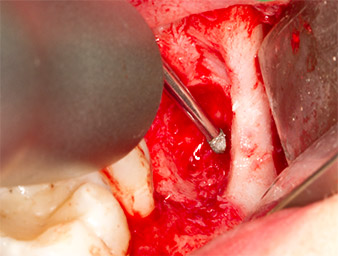

After block and local anaesthesia, the operating site was opened up and the soft tissue exposed for buccal retromolar access (Fig. 3).

The tissue above the root remnant was not completely ossified and consisted for the most part of granulation tissue modified by inflammation (Fig. 4).

To obtain autogenous material for subsequent wound treatment, healthy bone chips were harvested from the surroundings of the root remnant with a piezo surgical instrument (Piezomed B5) (Fig. 5).